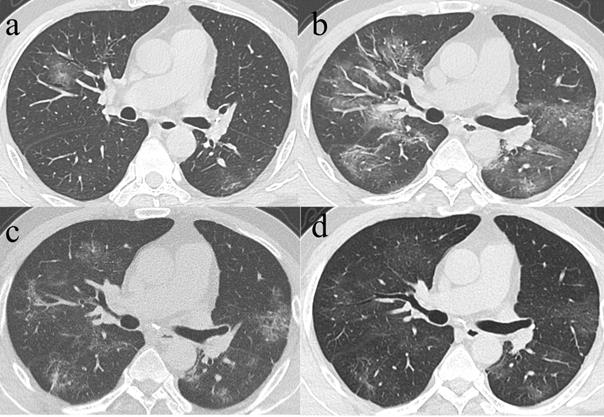

Among the 71 CT scans in Group 1 who had their initial CT taken within the 1st week of symptom onset, 8 patients with repeated examinations or no lesions were excluded, hence, 63 patients demonstrated CT abnormalities, including GGO in 38 patients, consolidation in 15 patients, and mix pattern for 10 patients. For the 38 patients with initial GGO, 37 presented varying residual lesions in the final scans, including GGO pattern [17 patients, median CT score: 3 (1, 7)] (Fig. 4), reticular pattern [18 patients, 9 (5, 13)] and mixed pattern [2 patients, 8 (5, 11)]. Noticeably, the median CT score of patients with the final reticular pattern was higher than that of patients with final GGO (p=0.004). Among the 38 patients with initial predominant GGO, 17 had final CT scan at discharge also demonstrated predominant GGO, while the median CT scores had significant differences between the initial [median CT score: 5 (3, 9)] and final CTs [median CT score: 3 (1, 7)] (p=0.033). On the other hand, 18 of the 38 patients had their initial predominant GGO turned to the reticular pattern in the final scans, for whom no significant differences were observed between the initial [median CT score: 8.5 (3.75,10.25)] and the final CT scores [median CT score: 9 (5,13)] (p=0.253). For the 15 patients with initial consolidation, residual lesions in the final scans were GGO in 9 patients [median CT score: 4 (2, 7)] and reticular in 4 patients [median CT score: 7 (3, 9.5)] (Fig. 5). For the 10 patients with initially mixed patterns, residual lesions in the final scans were GGO in 2 patients and reticulation in 7 patients [median CT score: 8 (2, 11)] (Table 3).

Figure 4

Series CT scans in a 61-year-old man with COVID-19 pneumonia. a. Scan obtained on illness days 2 showed GGO that affected the right middle lobe and left lower lobe. b, Scan obtained on illness days 9 showed an increased extent of GGO with little parenchymal bands. c. Scan obtained on illness days 19 showed absorption of abnormalities, with GGO and little parenchymal bands. d. Scan obtained on illness days 33 showed obvious absorption of abnormalities. Only GGO could be observed. The patient was discharged on illness days 36.